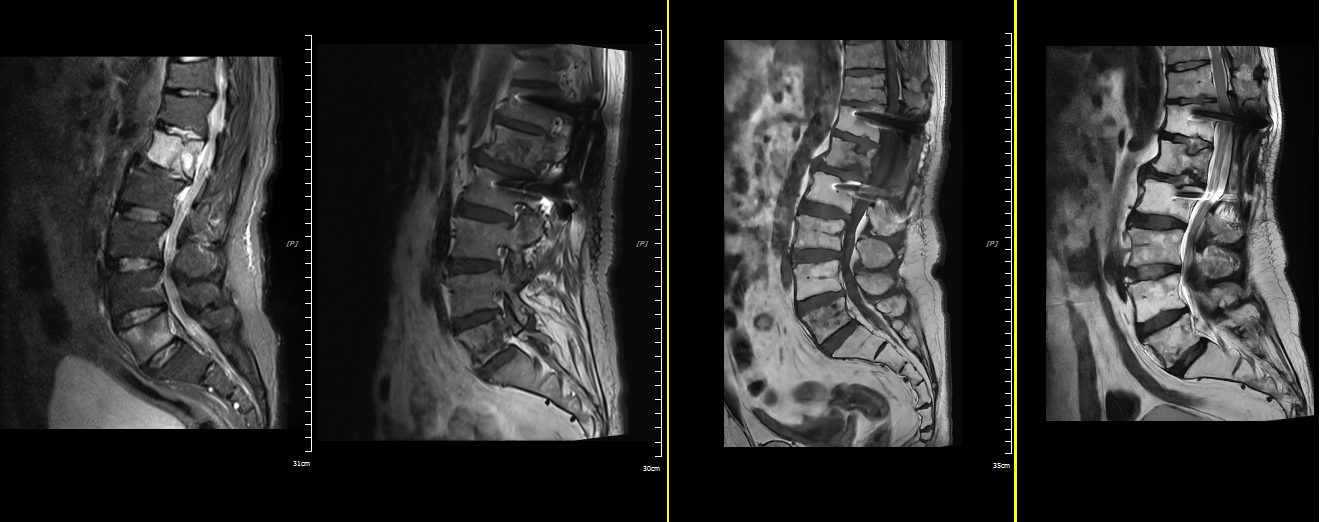

患者于2023年3月因腰背部疼痛,伴双下肢麻木,就诊于省级医院被确诊为左肺上叶低分化腺癌,胸椎、腰椎转移;当“肺癌晚期”“高位截瘫风险”字字如利刃般划破生活的平静时,我曾以为这是生命的终章。

在家人的陪同下我辗转来到武威肿瘤医院化疗科,在王慧娟主任及医护团队的精准治疗及帮助下,多学科协作先给予“经后路腰1椎管减压融合、神经松解内固定+腰5椎体骨水泥成形术”,后规律行“免疫联合姑息性化疗”治疗6周期,同时每28天给予唑来膦酸骨保护治疗;之后又给予胸腰椎体转移灶立体定向放疗(SBRT);后规律免疫维持治疗2年后病情稳定,停止治疗,直至目前已满3年病情持续稳定;当治疗结束时,我才惊觉:原来活着本身,就是最珍贵的礼物。